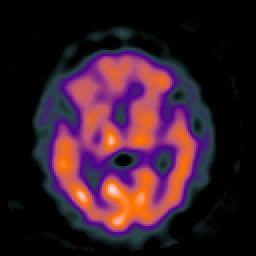

Huntington's Chorea, MR -- Slice #9

[Home][Help][Clinical] Slice 9